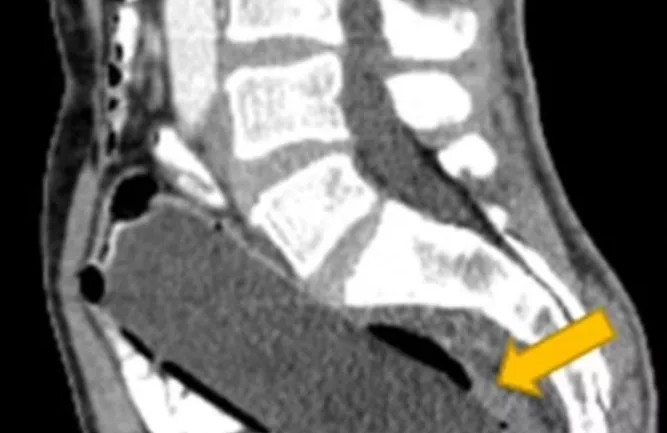

Ο άνδρας δεν είπε στους γιατρούς ότι αυτό συνέβαινε επειδή είχε μέσα του ένα μπουκάλι των 250ml. Το εντόπισαν μόνο όταν τον έστειλαν για αξονική τομογραφία. Γράφοντας στο περιοδικό «Clinical Case Reports», οι γιατροί είπαν ότι δεν ήθελε να αποκαλύψει ότι είχε βάλει το αντικείμενο μέσα του λόγω «αμηχανίας και φόβου για τη γυναίκα του».

Ο 50χρονος είχε σπρώξει πρώτα το κάτω μέρος του μπουκαλιού μέσα, ώστε να μπορεί να το βγάλει πιάνοντας το πάνω μέρος. Δυστυχώς, δεν μπόρεσε να βγάλει το αντικείμενο, αφήνοντας το πλαστικό μπουκάλι σφηνωμένο βαθιά μέσα στο παχύ έντερό του.

Ο άνδρας, ο οποίος είχε ιστορικό κατάθλιψης, μεταφέρθηκε αμέσως στο χειρουργείο και του χορηγήθηκε αναισθησία για να του αφαιρέσουν το μπουκάλι από το ορθό. Οι χειρουργοί προσεκτικά και αργά, όπως γράφει η «Daily Mail», έσυραν το μπουκάλι και δεν υπήρξε ρήξη ή αιμορραγία.